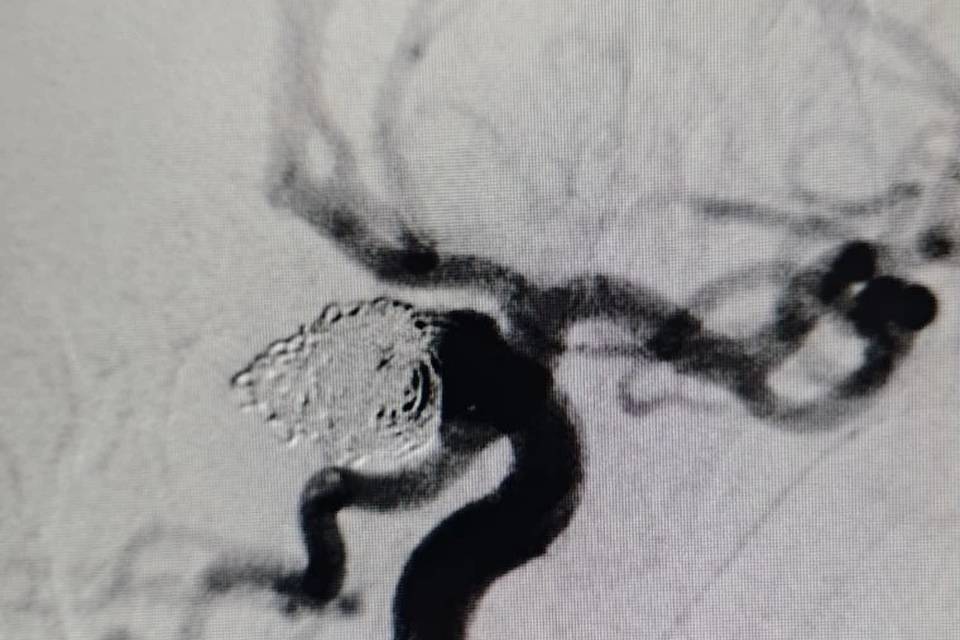

В Волгоградской областной клинической больнице № 1 эндоваскулярные хирурги провели экстренную высокотехнологичную малоинвазивную операцию молодой пациентке 43 лет с разрывом аневризмы головного мозга, — говорится в сообщении.

Операция заключалась в заполнении полости аневризмы микроспиралями. Это «выключает» сосудистое образование из кровотока, снижая риск разрыва и повторного кровоизлияния.